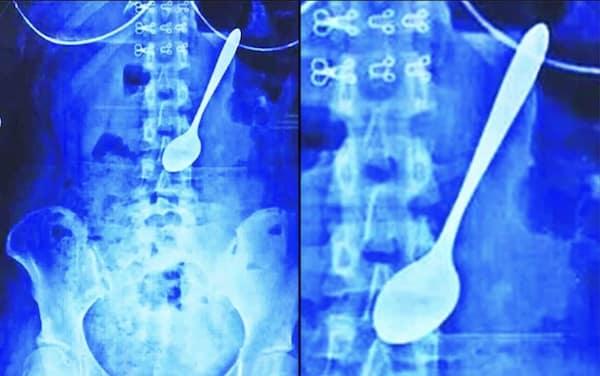

Weird xray photos

I used to think that nothing could surprise me anymore—until I stumbled upon some weird x-ray photos that made me reconsider my stance on human ingenuity (or lack thereof). Apparently, some people have a knack for getting objects lodged where they absolutely shouldn’t be. If you’ve ever wondered how not to use everyday items, these images might provide some unintended guidance.

This collection showcases 31 bizarre x-ray images that defy logic and anatomy textbooks alike. Each photo reveals unexpected objects making cameo appearances inside the human body, turning medical imaging into a gallery of the absurd. From common household items inexplicably found in unusual places to anomalies that would leave even seasoned doctors scratching their heads, these images offer a perplexing glimpse into the more “creative” side of medical emergencies. They highlight the intersection of curiosity, misadventure, and perhaps a dash of poor decision-making, all captured through the lens of radiology.